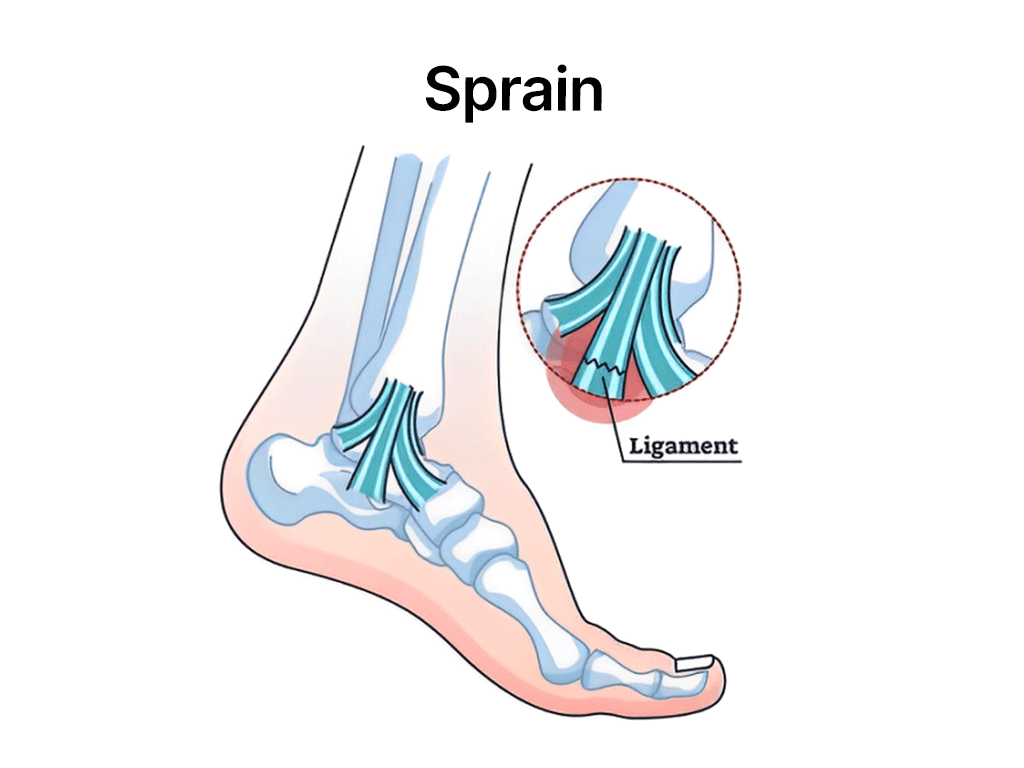

Acute sports injuries occur suddenly during activities. Examples include sprains, strains, fractures, and dislocations. Immediate steps can help manage the injury effectively:

Sprains

The most common types include sprains, strains, fractures, dislocations, tendinitis, and concussions.